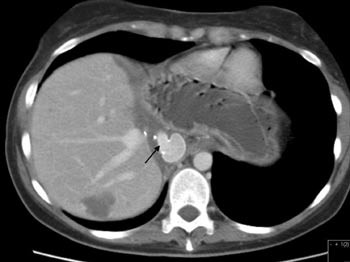

Pasient 1. 64 år gammel mann som ble utredet ved lokalsykehus for ukarakteristiske magesmerter. Ved abdominal CT var det blitt påvist en 6 x 6 x7 cm stor tumor beliggende mot leverens bakside, muligvis i segment 1. V. cava var sterkt komprimert og på det nærmeste okkludert av denne tumoren (fig 1). Tumoren ble initialt oppfattet som et leverneoplasme. Grunnet relasjonen til v. cava ble tilstanden ansett som utilgjengelig for kirurgi, men pasienten ble henvist til Rikshospitalets Seksjon for gastroenterologisk kirurgi til vurdering (second opinion). Biopsimateriale fra tumoren ble av ett laboratorium med et visst forbehold beskrevet å være fra et leiomyom. Et annet laboratorium mente det dreide seg om et schwannom. Antatt risiko for forestående okklusjon av vitale leverkar samt en sannsynlighet for at det dreide seg om et malignt neoplasme gjorde at man ble enig om å forsøke kirurgisk fjerning av tumor. Rutinemessige preoperative blodprøver viste normale verdier (e-tab 1).